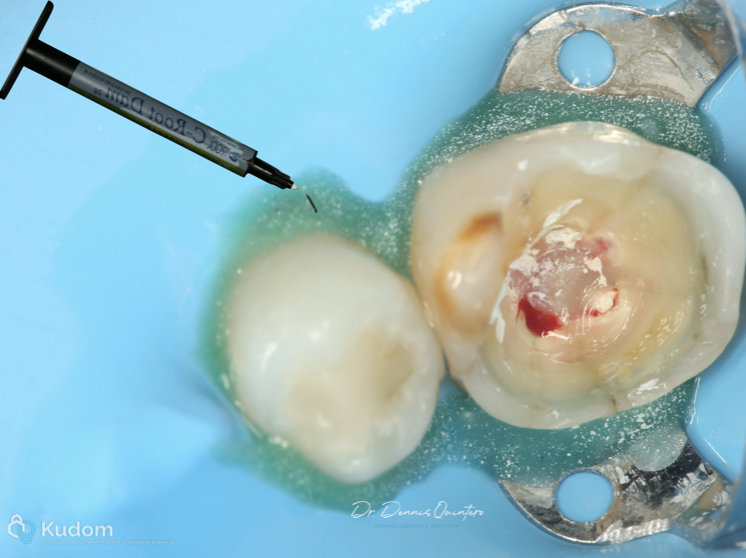

Fig. 5

. We start with isolation and the use to C-Root Dam to avoid saliva filtration.

Fig. 6

C-Root Dam use to seal around the tooth with isolation and avoid filtration.